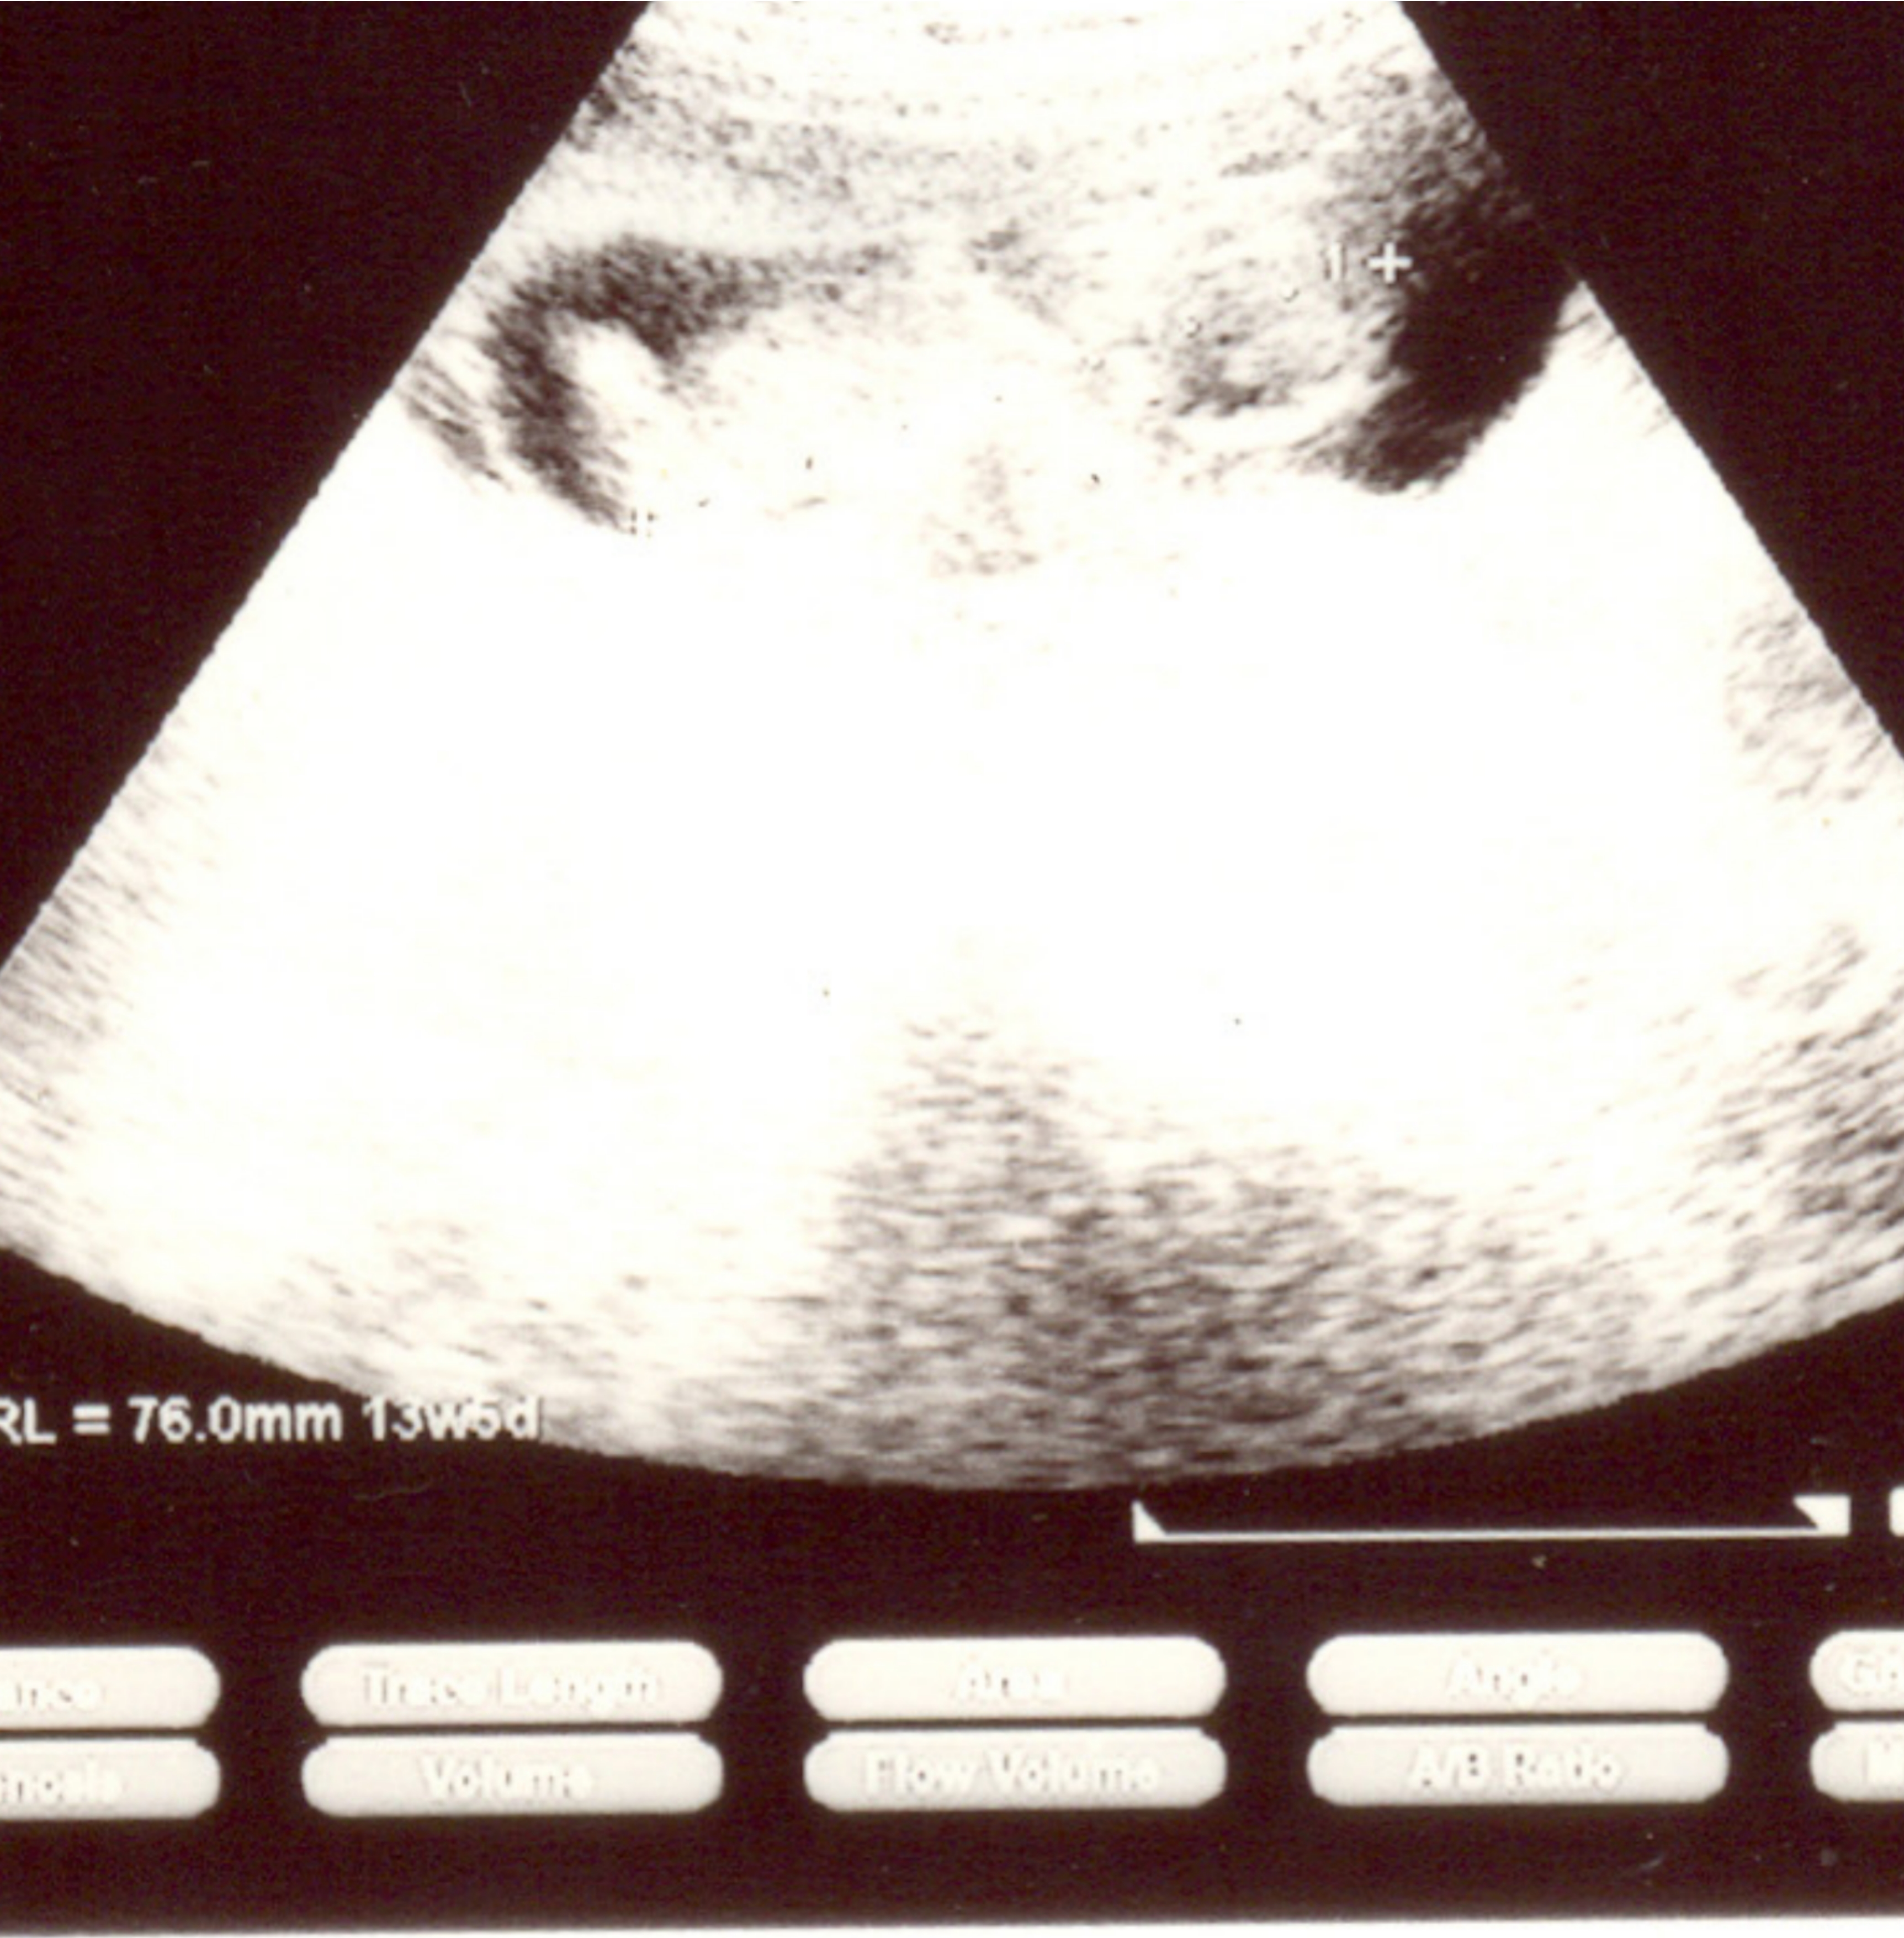

13week & 5days ultrasound pic here.plz help to guess G or B?Attachment 16333

Sorry, I can't even tell what I'm looking at. Not a clear pic.

Too difficult to see baby or nub.